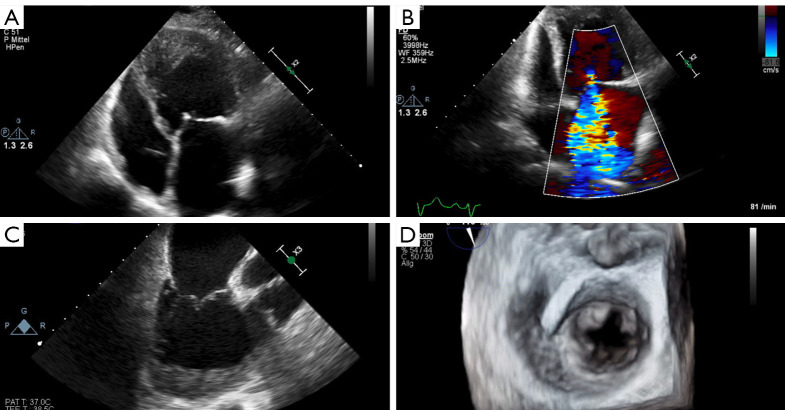

Abstract Image